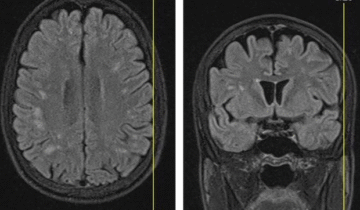

Advanced Imaging

Neurology